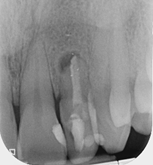

Root canal retreatment and bypass of separated instrument

Pre-op

12 month review demonstrating healing